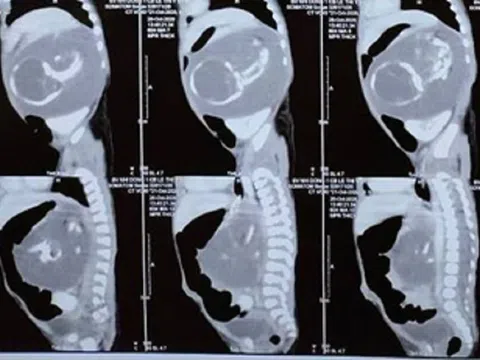

Bé trai chào đời mang theo người em song sinh… trong bụng

hào đời với khối u có kích thước lớn trong bụng, bác sĩ xác định đó chính là người em song sinh của bệnh nhi. Cuộc phẫu thuật thành công đã trả lại cho bé cơ thể bình thường.